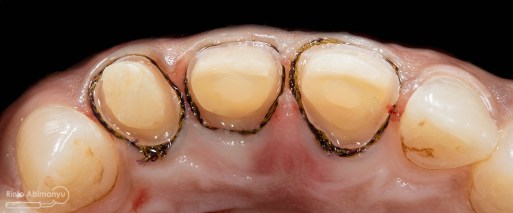

Kemudian preparasi pembuatan crown dimulai… Saya menggunakan bur silindris diameter kecil dengan ujung round sehingga untuk membentuk tepi preparasi menjadi chamfer akan lebih mudah… Selesai preparasi dilanjutkan dengan pemolesan hasil preparasi agar halus dan tidak mengganggu saat pencetakan.. Kemudian dipasangkan retraction cord nomer 00.

ini hasil preparasi gigi-giginya…